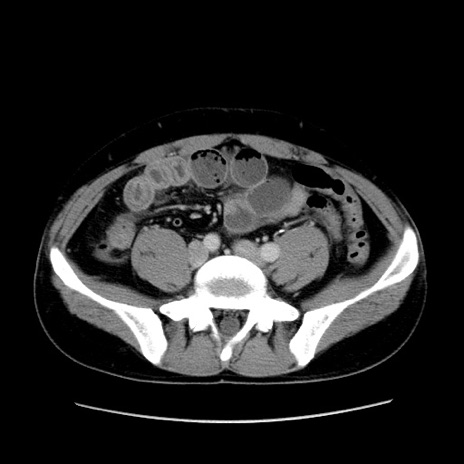

冠状断像

【症例】30歳代男性

【主訴】腹痛、嘔吐

【現病歴】昨晩から突然の腹痛あり、その後嘔吐、軟便も出現。腹痛が改善しないため救急搬送となる。2日前にしめ鯖の食事歴あり。

【身体所見】意識清明、苦悶様、BP 135/90mmHg、BT 35.7℃、腹部:平坦、やや硬、心窩部〜臍部に自発痛、圧痛あり、筋性防御+、反跳痛-

【データ】WBC 8100、CRP 0.57